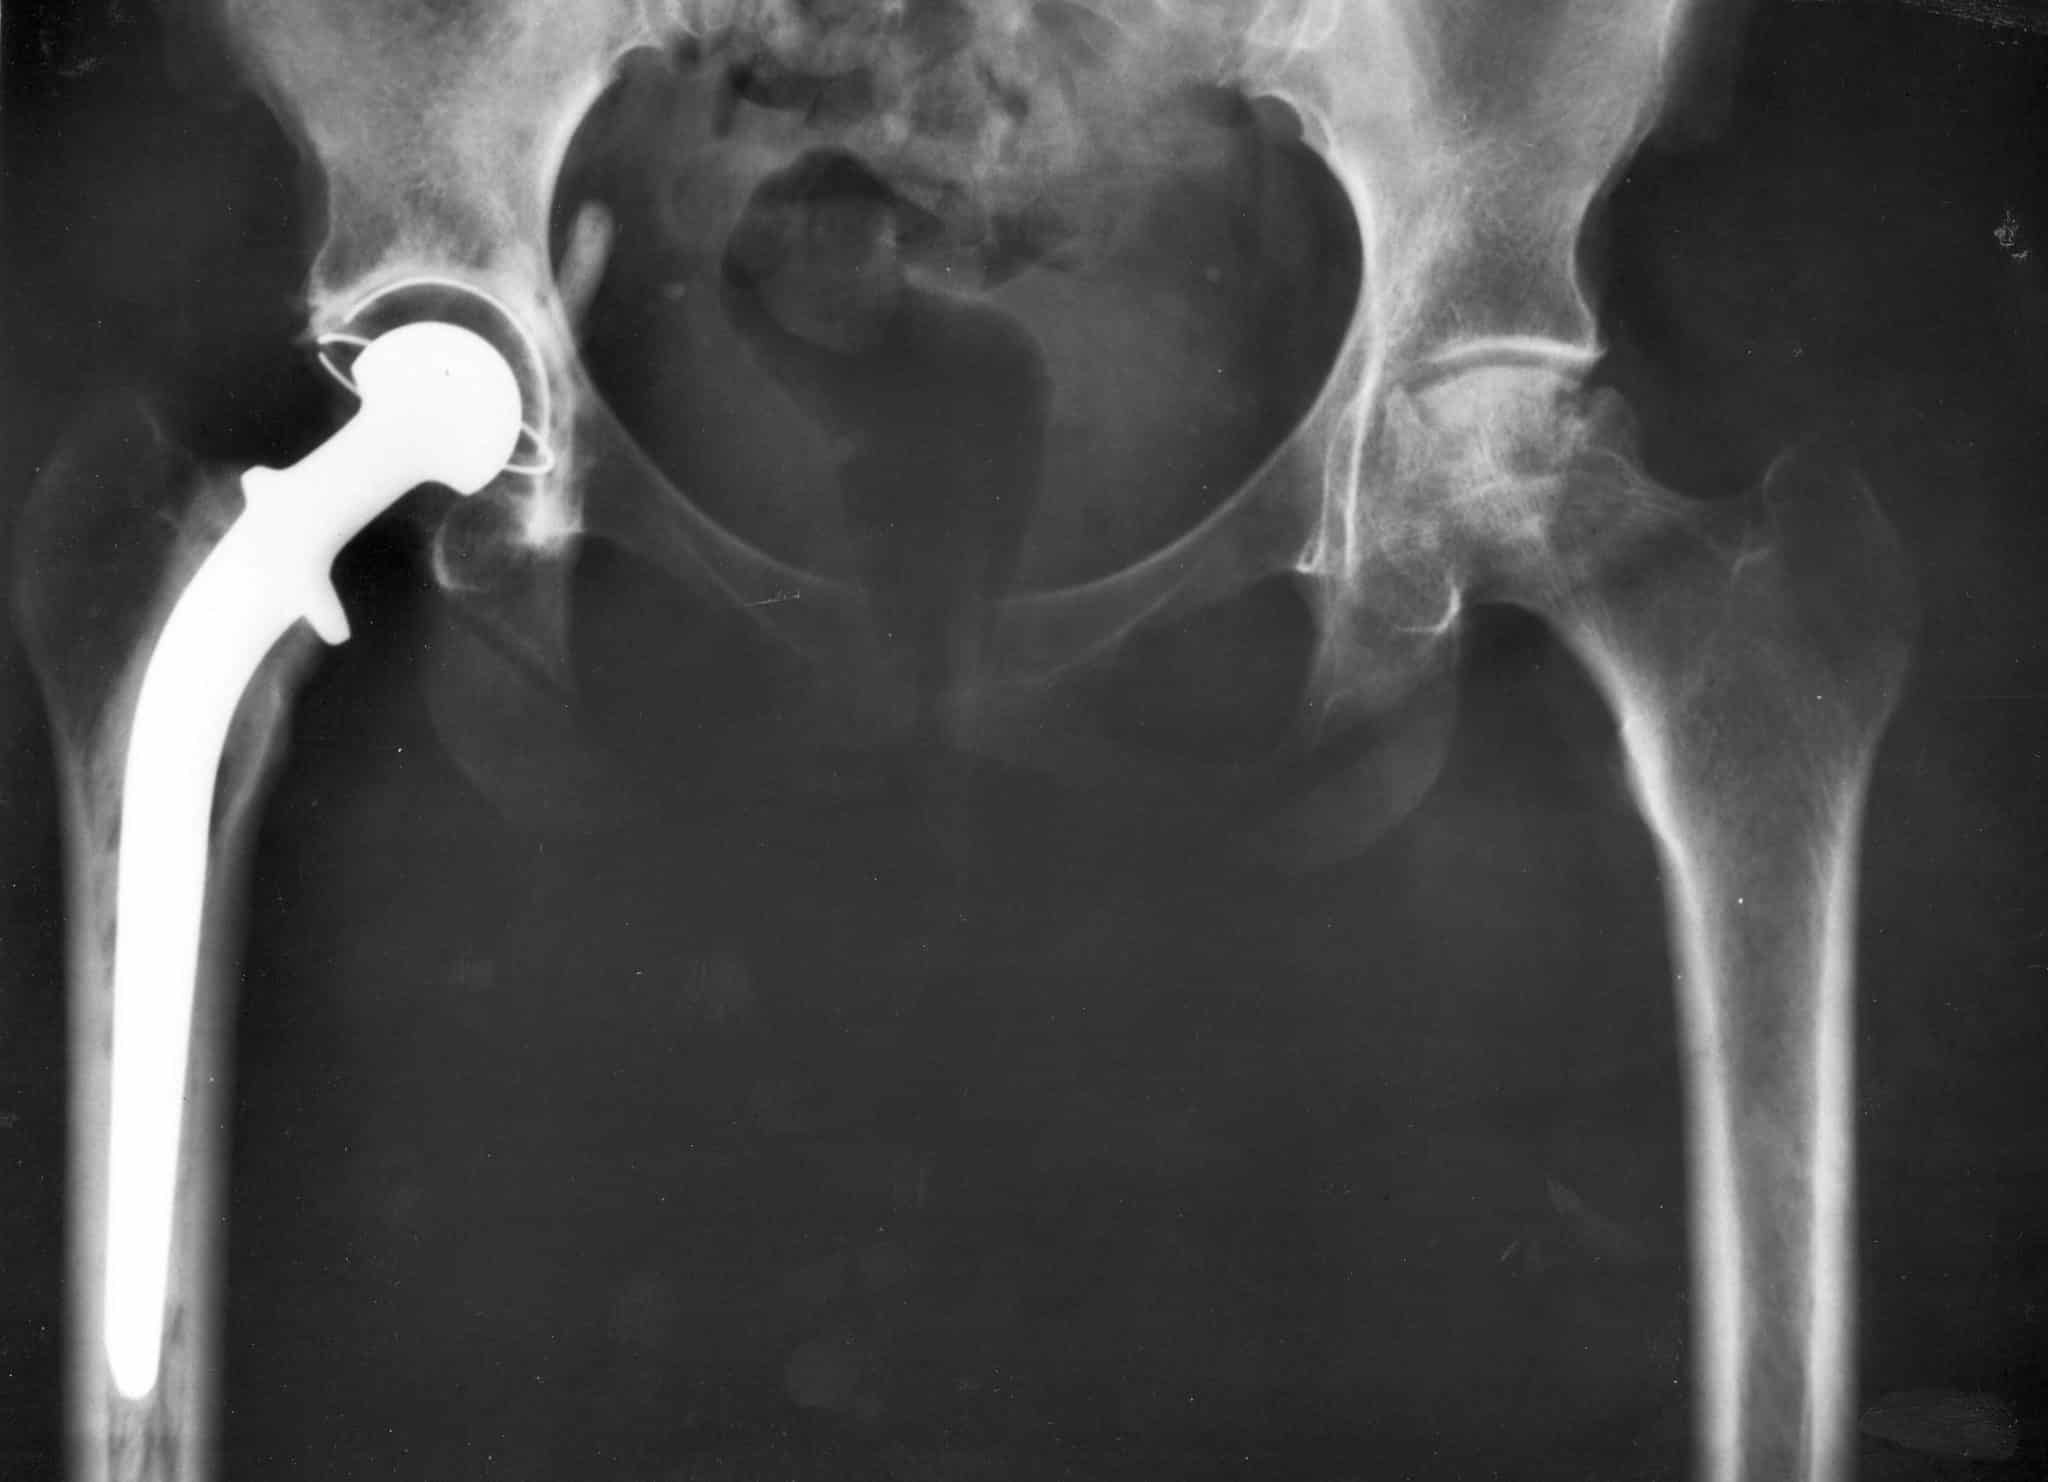

Современная медицина достигла значительных результатов в области замены поврежденных суставов. Подобные операции сегодня стали высокоточными процедурами, позволяющими пациентам не просто избавиться от хронической боли, а вернуться к полноценной активной жизни. По последним данным, примерно 200 тысяч человек в России ежегодно нуждаются в полной замене тазобедренного сустава. Такая потребность делает важным не только доступность самой операции, но и создание имплантатов, которые служили бы десятилетиями без риска отторжения и повторных операций.

Проблема в том, что существующие металлические протезы остаются чужеродными для организма. Большинство материалов, которые используют врачи, в 4-5 раз жестче натуральной кости. Эта разница приводит к медленному разрушению тканей вокруг имплантата, его расшатыванию и необходимости повторной операции.